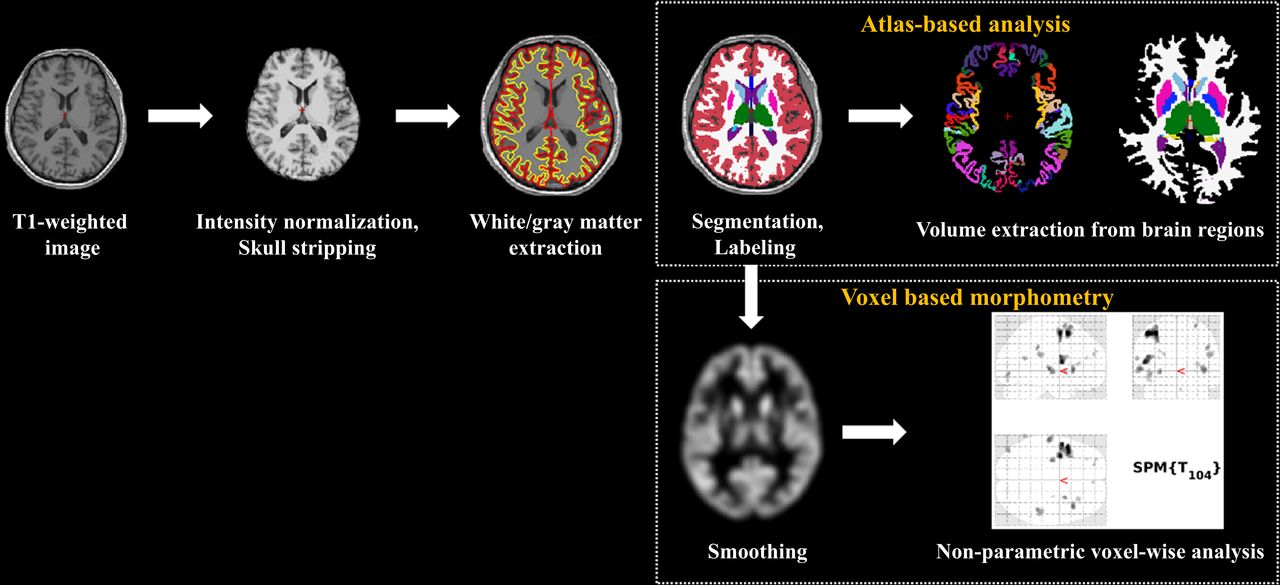

Що саме змінюється у мозку?Дослідники з Університету Чхун-Анг та Університету Йонсей у Південній Кореї провели спостереження за 110 медичними працівниками. Частина з них працювала за стандартним графіком, інша - понад 52 години на тиждень (саме таку межу встановлено законом у Південній Кореї).

У групі "перепрацьовуючих" виявили значні зміни в об'ємі сірої речовини - в тих ділянках мозку, які відповідають за:

- увагу

- пам’ять

- контроль емоцій

- когнітивні функції (мислення, прийняття рішень).

Йдеться зокрема про лобову звивину та острівець - зони, що впливають на нашу здатність концентруватися, спілкуватися, розуміти емоції та реагувати на стрес.

Які зміни відбувають в мозку (фото: oem.bmj.com)

Які зміни відбувають в мозку (фото: oem.bmj.com)